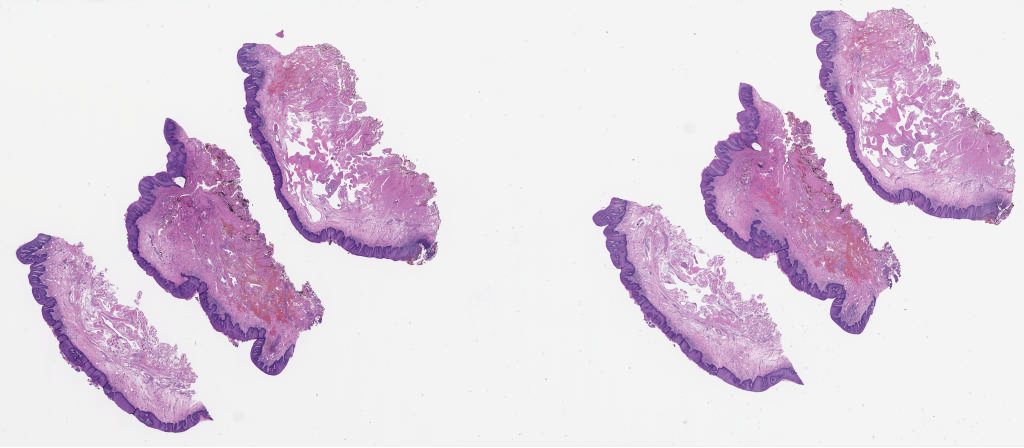

University of Pittsburgh Oral Pathology Study Set Summer 2025\Case04

1867740.svs